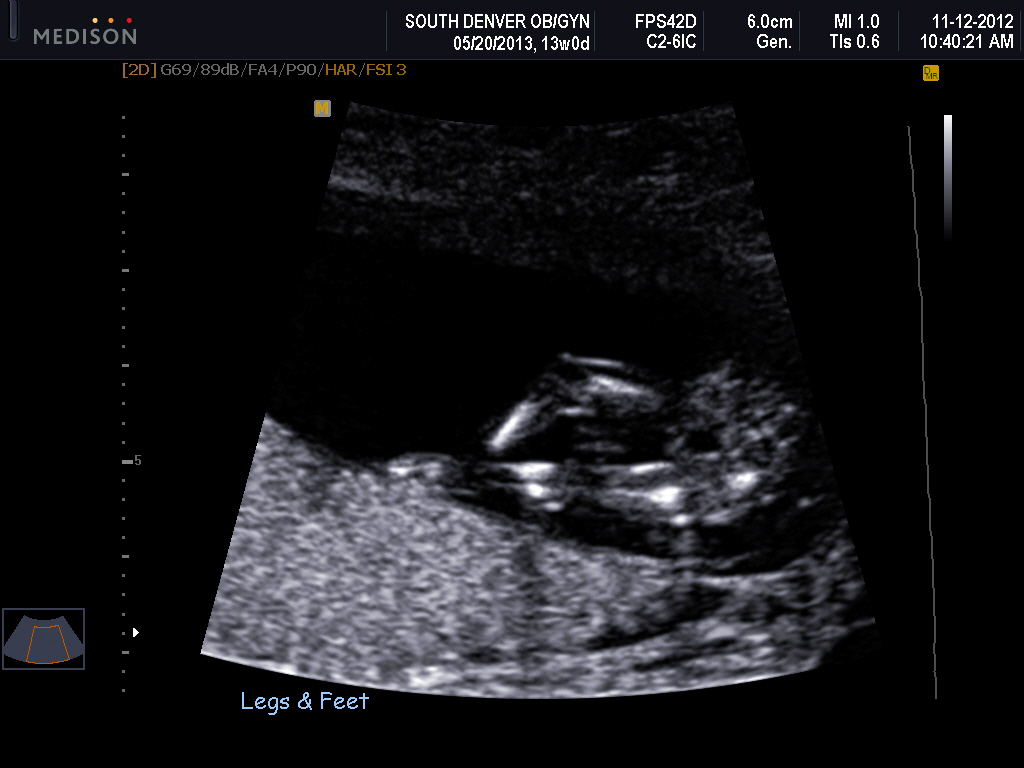

Attachment 6203Attachment 6204Attachment 6205

I had a video but not sure how to upload it. I had a potty shot on the video and I know they are not as accurate now but it sure looked like a boy. Does anybody know how to add a video?